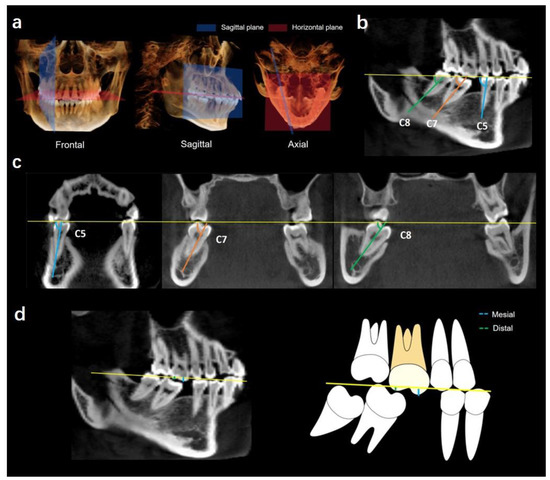

2.1. Determination of Coordinate Planes

2.2.1. Angulations of Bilateral Mandibular Posterior Teeth

Mesiodistal Angulation

Buccolingual Angulation

2.2.2. Extrusion of Maxillary First Molars

2.2.3. Alveolar Bone Loss in the Missing Tooth Region

Vertical Alveolar Bone Loss in Missing Tooth Region

Horizontal Alveolar Bone Loss in Missing Tooth Region